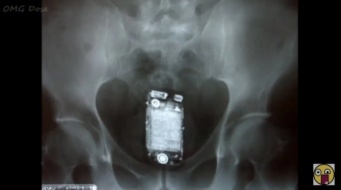

「2019年、アメリカ人が体の“穴”に入れてしまった様々なモノ」のページです。デイリーニュースオンラインは、社会などの最新ニュースを毎日配信しています。